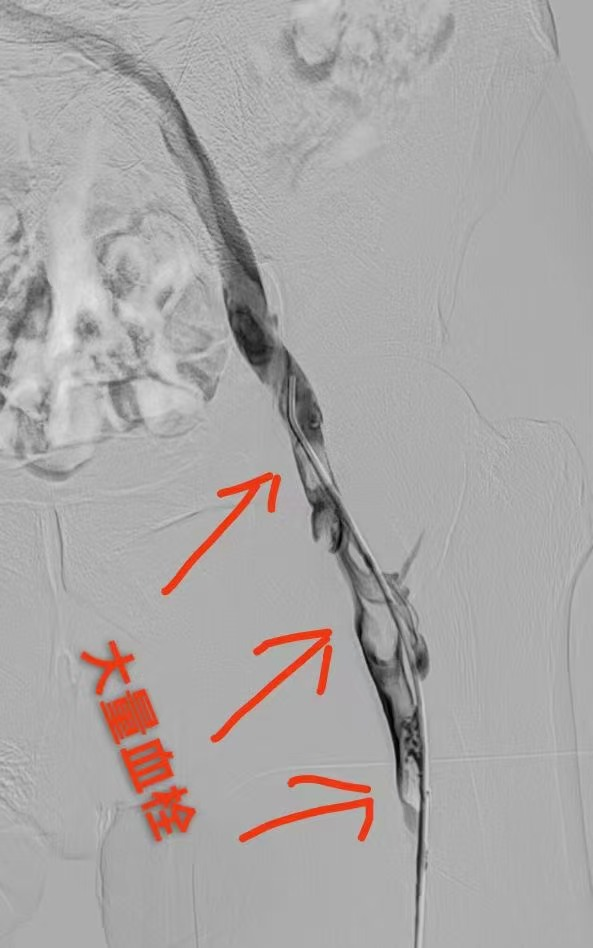

圖一為下肢血栓形成影像圖片 圖二為與圖一同部位經(jīng)過治療后血栓消失照片(圖片來源網(wǎng)絡(luò),如有侵權(quán)聯(lián)系刪除)

接下來就讓我們一起探索神奇的血栓消失過程,了解血栓的歸處旅程吧!血栓一般分為動脈血栓和靜脈血栓,動脈血栓進展較快,后果也相對嚴重,會引起急性癥狀,并會短時間內(nèi)危機生命或?qū)е聡乐厣眢w損傷等,大部分動脈血栓的患者都需手術(shù)治療方式予以及時緊急干預(yù),如腦血栓、冠脈血栓、腸系膜動脈血栓、下肢動脈血栓等。相對于動脈血栓,靜脈血栓的患者的危急情況會稍好一些,無需緊急手術(shù)治療,可采用多種干預(yù)措施,當然根據(jù)病情進展情況,手術(shù)治療也是重要的備選方案,通常情況是使用注射或者口服抗凝藥物治療,如腸系膜靜脈血栓、下肢深靜脈血栓、上肢靜脈、門靜脈、卵巢靜脈等情況。??

歸處一:血栓溶解、吸收或軟化;水管里新鮮的雜質(zhì)會隨著水流和壓力的增強稀釋溶解,靜脈血栓同理也會隨著血容量的增加及自身纖溶系統(tǒng)而稀釋或者溶解。新近形成的血栓,血栓內(nèi)會產(chǎn)生纖維蛋白溶解酶等,可以促使血栓軟化并逐漸溶解,血栓是可以自行溶解的。而血栓的溶解快慢或者程度,取決于血栓的大小和新舊程度,血栓越新鮮,自身基礎(chǔ)因素越好血栓越容易溶解。血栓形成的同時,纖溶系統(tǒng)也不同程度地被激活,血栓中的纖維蛋白吸附大量纖溶酶,也可使血栓溶解軟化;血漿內(nèi)正常存在的纖溶酶原被纖溶酶原激活劑激活成纖溶酶,與纖維素結(jié)合的纖溶酶可將纖維蛋白溶解。小而新鮮的血栓在特定情況下可完全溶解,這就是部分血栓患者,如下肢肌間靜脈血栓,單純使用藥物抗凝治療,就能取得很好效果的原因之一。但較大的血栓則不能被完全吸收從而被機化,或由于部分發(fā)生軟化,被血液沖擊可形成碎片狀或整個脫落,形成栓子隨血流運行,引起栓塞。這類似水管里的淤泥等雜質(zhì)較多時,一些雜質(zhì)會被稀釋或溶解,還有一些會松動或脫落,然后隨著水管里的水流被沖走。溶解脫落的血栓會隨著血液流到其它組織器官中,然后卡在與血栓大小相應(yīng)的血管中造成血栓栓塞。這也是下肢深靜脈血栓會順著血管方向脫落堵塞肺部的血管造成肺栓塞的原因之一。就像城市停水后,我們會發(fā)現(xiàn)水龍頭里會有泥水的情況,就是因為水管里的淤泥等雜質(zhì)隨著水流和壓力的恢復(fù),分散溶解在水中流到千家萬戶(毛細血管)一樣。